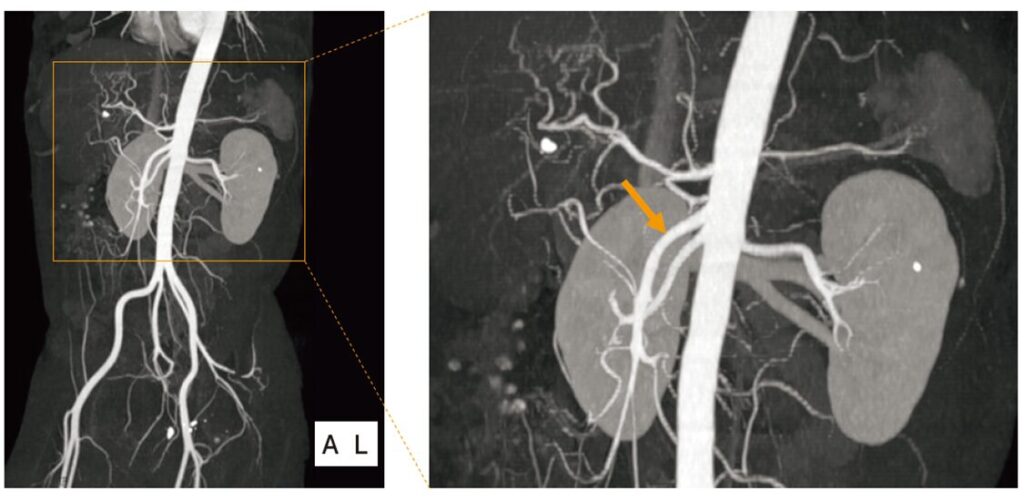

腹部造影CTのMIP像を示す。矢印で示すのはどれか。

提示されている画像は、造影CTの「MIP(最大値投影:ミップ)像」です。

これは、造影剤で白く染まった血管だけを抽出して、レントゲン写真のように透かして重ね合わせた画像です。血管の全体的な走行を見るのに非常に適しています。

✔ 矢印の血管を特定する

オレンジ色の矢印が指している血管は、腹部大動脈から出て「足側(下)に向かってスッと伸びて」いますね。 また、左右の腎臓に向かって横に伸びている血管(腎動脈)と、ほぼ同じ高さから起始して、腎動脈の前をクロスするように下へ向かっています。

この「大動脈の前から出て、下に向かって長く伸びる」という走行の特徴は、まさに上腸間膜動脈(SMA)です。

- 大動脈の「側面」から、左右の腎臓に向かって「横」に伸びる血管です。画像でも、矢印の血管の後ろ側から左右の腎臓(ソラマメ型の白い臓器)に向かって伸びているのが分かります。

- 腹腔動脈から枝分かれし、左側にある脾臓に向かって「蛇行しながら(クネクネと)」伸びる血管です。

- 矢印の血管(上腸間膜動脈)のすぐ「上」から出る血管です。

- 腹部大動脈が一番下(へその下あたり)で「左右に二又に分かれた後」の血管です。